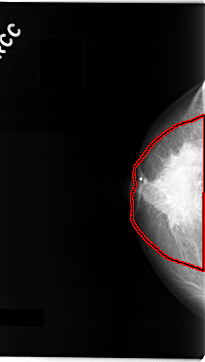

C_0061_1.RIGHT_CC

RIGHT_CC LINES 4704 PIXELS_PER_LINE 2664 BITS_PER_PIXEL 12 RESOLUTION 50 OVERLAY

FILE: C_0061_1.RIGHT_CC.OVERLAY

TOTAL_ABNORMALITIES 1

ABNORMALITY 1

LESION_TYPE MASS SHAPE IRREGULAR MARGINS SPICULATED

ASSESSMENT 5

SUBTLETY 5

PATHOLOGY MALIGNANT

TOTAL_OUTLINES 1

BOUNDARY